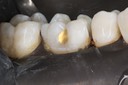

Kyle Chock #2 pre-op

Kyle Chock #2 composite removal

Kyle Chock #2 prep